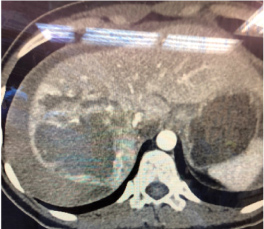

Overnight, C.M. had a vasovagal event as she used the bathroom; she did not fall or further injure herself during the event. However, she was found to have nausea and emesis during our morning rounds. When reassessed later that day, C.M. had worsening abdominal discomfort with persistent nausea. A CT scan was performed that revealed a larger liver laceration when compared to the CT scan from the outside hospital as well as extensive hemoperitoneum (Figure 1). C.M. was evaluated by the surgical team, and operative management was elected to control her bleeding, debride her liver injury, and evacuate the hemoperitoneum. The patient was informed of the findings and consented to the procedure. Blood was ordered on-call, and the operating room was informed of the emergency procedure.

Figure 1: CT scan showing significant liver laceration with extensive hemoperitoneum. View Figure 1